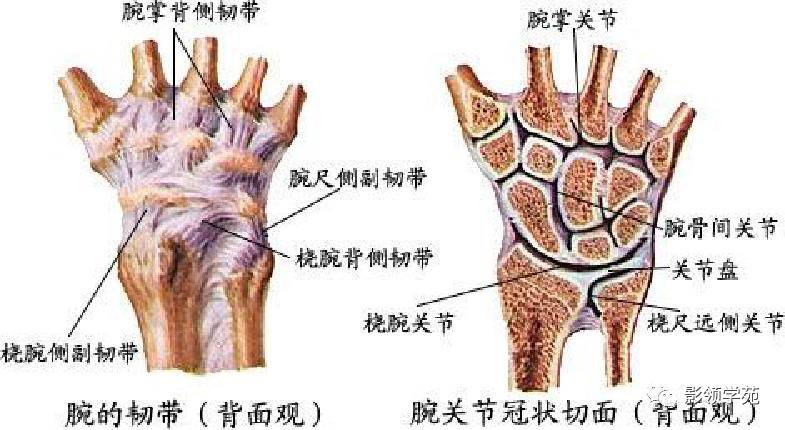

关节与韧带系统

韧带系统

关节与韧带系统

韧带系统